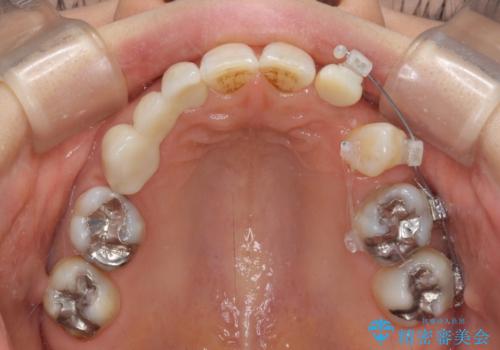

ブリッジによる補綴治療にて、欠損や隙間を補完することとしましたが、神経を取り除いたり、審美的に不自然になることを避けるため、部分矯正を併用することとしました。

隙間が全て閉じたことで、長年食事の度に挟まる不快感が改善されました。

また、正面から見た印象がまるで自分の歯であるような自然な仕上がりとなりました。